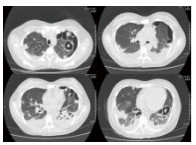

入院相关化验结果,血常规:WBC 0.8 g/L, NE 0.5 g/L, HGB 126.0 g/L, PLT 47.0/L;血气分析:pH 7.450,PaCO2 32.90 mmHg,PaO2 52.50 mmHg,SaO2 89.3%, LAC 3.9 mmol/L, HCO3- 22.5 mmol/L;心肌标志物:CK 4 668 U/L,MB 46.2 ng/mL,cTnI 0.52 ng/mL,MyO 1 884 ng/mL;肾功能:UREA 7.10 mmol/L,CREA 80.7 μmol/L,Glu 8.35 mmol/L,Na+ 131 mmol/L,K+ 3.9 mmol/L;肝功能:ALT 47 U/L,AST 211 U/L,ALB 22.4 g/L,TBIL32.93 μmol/L,DBIL 19.01 μmol/L; D-Dimer 18 893 μg/mL;BNP 986 pg/mL;ESR 66 mm/h;CRP 320 mg/L; 降钙素原53.8 ng/mL。腹部B超(-);子宫附件B超(-);超声心动图(-)、入院前胸部CT平扫提示双肺多发片状、团块病灶,见图 1。

| 图 1 入院前胸部CT |

2.4 影像学除外肺部转移瘤的原因分析患者住院时高热,喘憋比较明显,影像学提示双肺弥漫性浸润病灶(图 1)。最初考虑可能为多发肺部转移瘤?随着治疗的好转以及影像学的演变,最终排除了肺部转移瘤的诊断。

MSSA的影像学特点是在疾病早期,CT改变不明显,仅有小片状肺部浸润,但是,病变发展极快,出现大叶性炎症改变或肺段性浸润,以双下肺野多见。随后病灶内或其周围出现空腔或蜂窝状透亮区,并可发展为肺脓肿。肺浸润、肺脓肿、肺气囊肿和脓胸或脓气胸为金黄色葡萄球菌肺炎的四大影像征象,不同病期以不同的组合表现。肺气囊肿为金黄色葡萄球菌肺炎的典型影像学表现,是支气管周围脓肿使终末细支气管和肺泡发生坏死,当与支气管相通后坏死物质排空形成的直径1~2.5 cm、壁厚1~2 mm、圆形或类圆形薄壁空腔,多发者似蜂窝肺。当临床表现已明显缓解时肺气囊肿仍可存在数月,最后可自然痊愈。

这例患者的疾病过程以及胸部CT表现符合上述改变,“毁损的肺组织”是肺气囊肿,后期随着病情的好转,肺组织基本恢复正常。